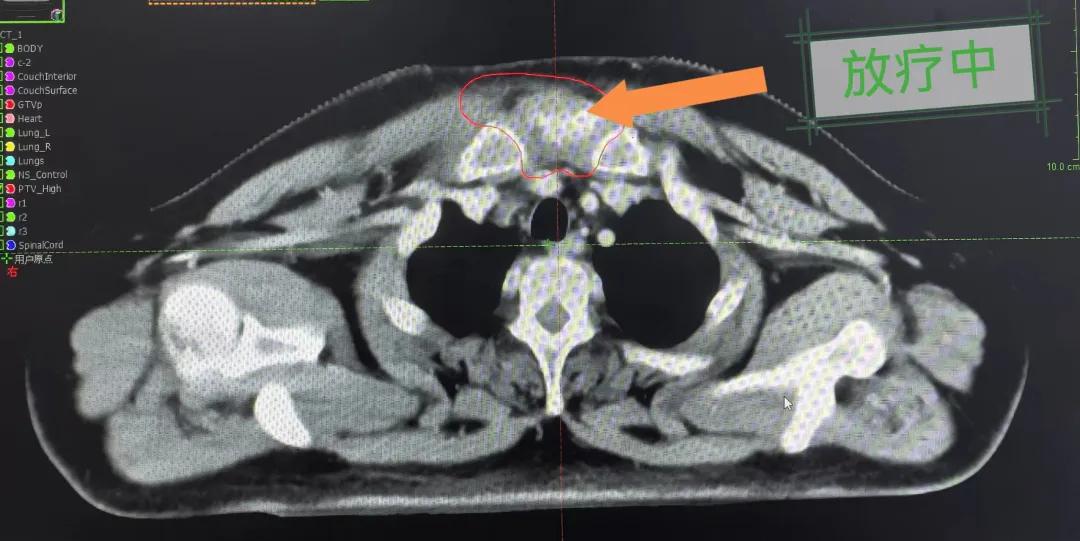

隨后,趙亮主任帶領(lǐng)放療團隊以最快的速度完成了患者的放射治療計劃,在保證放療精準打擊腫瘤的同時,利用先進的三維立體精確放療技術(shù),最大限度的避免心臟、肺部的損傷發(fā)生,整體治療精準度達到1mm以內(nèi)。經(jīng)過10次的放射治療后,患者疼痛已明顯減輕,胸部腫物肉眼可見的縮小,患者及家屬臉上終于露出久違的笑臉。

治療期間,患者沒有出現(xiàn)明顯不適,治療結(jié)束后,患者胸壁腫物由最初8cm縮小至約1cm,后患者至外科行手術(shù)治療。